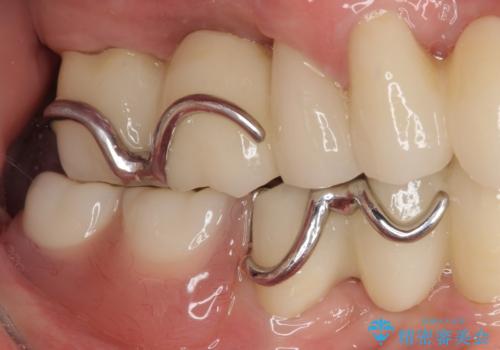

装着感の良い入れ歯を作りたい 金属床を使用した適合の良い部分床義歯

より適合の良い義歯とするため、セラミッククラウンなどは義歯の設計に合わせた土台の歯となるよう全て再製作をし、安定感に優れた義歯を製作することができました。